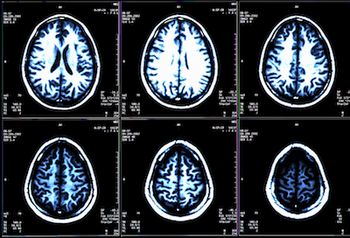

Multiple Sclerosis

Prompt diagnosis and timely intervention is key in improving outcomes for patients with multiple sclerosis (MS). A new study in Multiple Sclerosis Journal outlines quality standards for timely, brain health–focused MS care.

Researchers used a blood test to look for biomarkers indicative of Alzheimer disease in a group of people with a genetic mutation for a familial form of the disease, and they said the test can predict differences about 16 years before affected patients are expected to begin showing symptoms. The hope is that a blood test could one day be used to identify brain disease for not only Alzheimer disease but also other neurodegenerative conditions, such as multiple sclerosis, traumatic brain injury, or stroke.